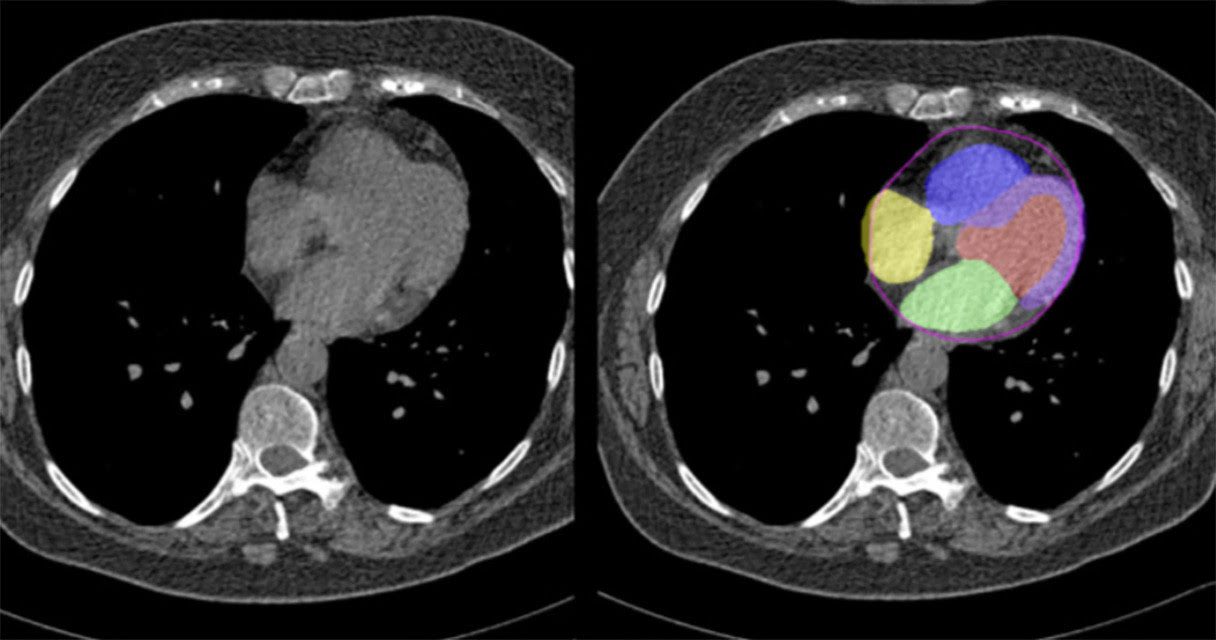

Cedars Sinai Researchers Uses AI to Analyze Regular Chest CT Scans to Predict Heart Disease Risk

April 24, 2024April 25, 2024HIT Consultant

What You Should Know:

– Researchers at Cedars-Sinai have developed a new method using artificial intelligence (AI) to assess cardiovascular disease risk during a routine chest computed tomography (CT) scan without contrast dye.

– The recent…